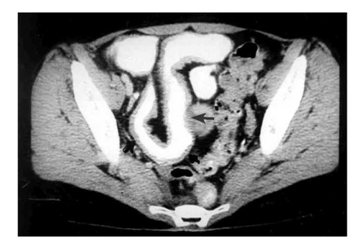

האבחון הרנטגני הוא חשוב. צילום בליעת בריום, אנטרוקליזיס וטומוגרפיה ממוחשבת של הבטן עם בליעת חומר ניגוד הם הכלים העיקריים לאבחנה. קשת של סימנים מצביעה על פתולוגיה במעי הדק.

- הדופן מעובה, ולכן המרחק בין הלולאות הוא רב (תצלום 15.5).

- הרירית מאבדת את המבנה הרגיל שלה ואפשר לזהות בה פיסורות, תבנית אבני מרצפת, חריגויות ואי-סימטריה (תצלום -17.4 ו-18.4).